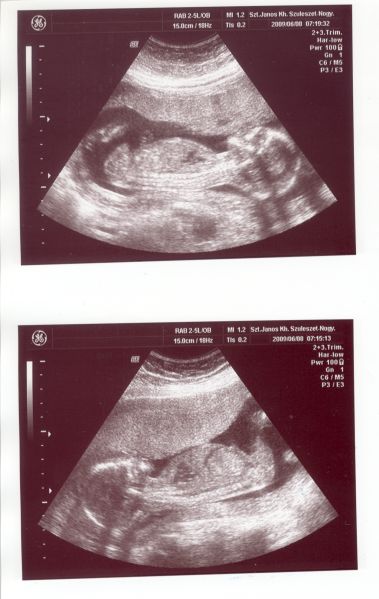

Rilla, remélem nálunk is behozza magát a lurkó. Eddig mindig 2 nappal idősebb volt a leleteken, most meg fiatalabb, de gondolom 1 hét még nem okoz gondot.